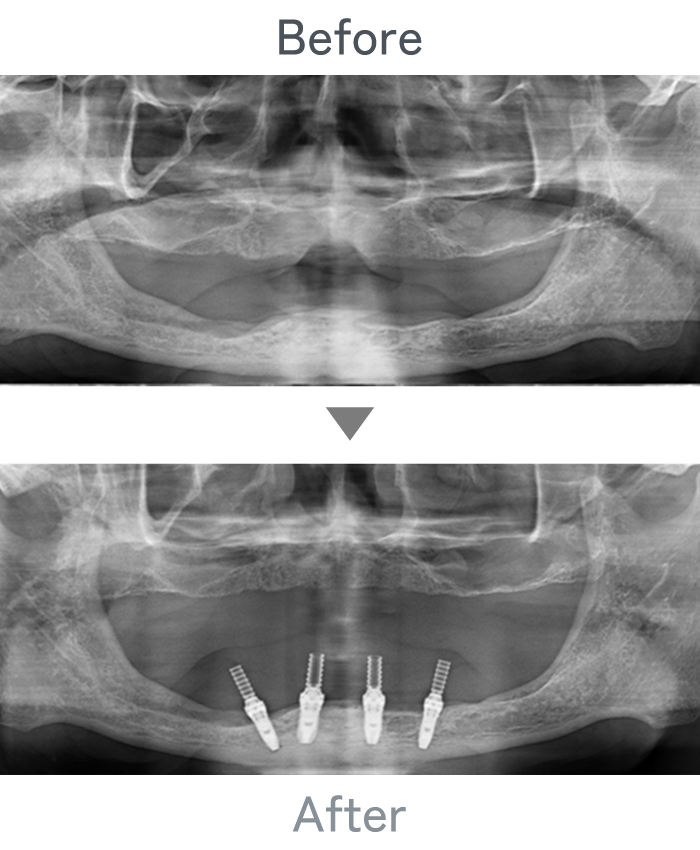

All-on-4

+

金属床義歯

主訴 入れ歯が使えなくて固定式にしたい

治療法 上顎:金属床義歯

下顎:All-on-4

治療期間 4ヶ月

※仮歯は手術当日に装着

費用 ・上顎金属床義歯:200,000円

・下顎All-on-4:2,500,000円

小 計:2,700,000円

消費税:270,000円

合 計:2,970,000円

※インプラント体、上部構造ともに『10年保証』

副作用

• メンテナンスが必要